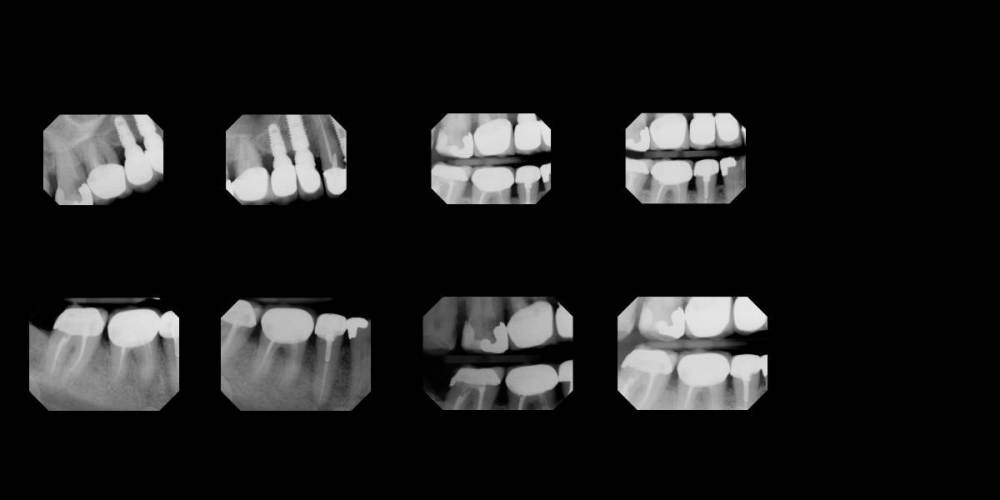

Зуб #2 Какое лкчение наиболее правильное?

Если по предлагаемому снимку можно увидеть то прошу сказать

Какое лечение наиболее правильное для зуба #2 ?

1.Пломбирование +коронка?

2..Удаление нерва +пломбирование +коронка?

3.Удаление зуба?

#1  #2   #30.jpeg

Мы же с Вами обсудили, что нужно больше данных. Составлять план исходя только из этих снимков не верно.